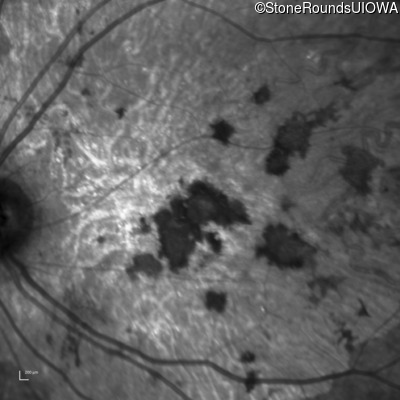

Infrared Fundus Photograph - Left - 20/300 sc

Exemplar